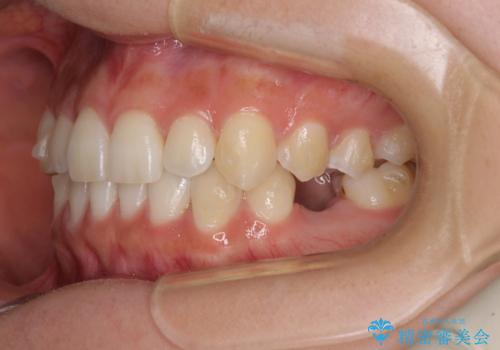

左下には後続永久歯の欠損した乳歯が残存しており、叢生を相まって咬合関係が乱れていました。

乳歯は抜歯し、インビザラインにて矯正治療を行いながら、並行してインプラントによる補綴治療を行うこととしました。

矯正治療が終わるタイミングに合わせてインプラントの埋入を行っていたので、矯正治療を終了すると同時にセラミック補綴治療を行えました。

短期間でしっかりと治療を終えることができました。